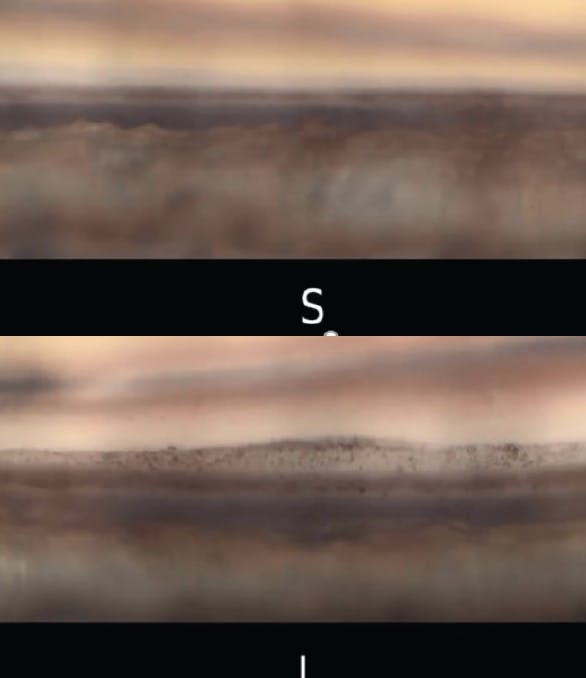

Figure 2. More pigment is present in the inferior angle (I) than in the superior angle (S). Image captured with the GS-1 Gonioscope (Nidek).

Contact between the anterior lens capsule, the zonules, and the iris disrupts the iris pigment epithelium, distributing pigment throughout the anterior chamber. Pigmentation of the trabecular meshwork increases as a result, more inferiorly than superiorly (Figure 2).